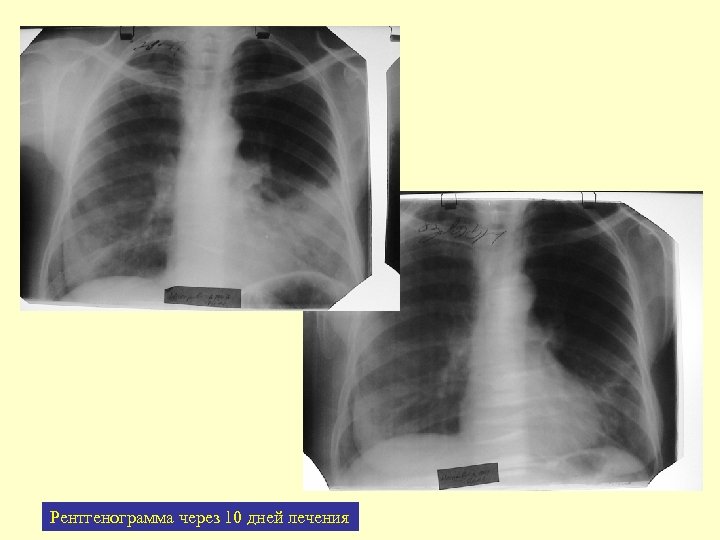

Рентгенограмма через 10 дней лечения

Б-я Ш. , 17 лет per os 10 дней

Динамика 10 дней